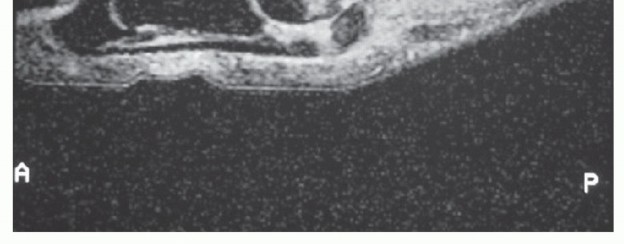

Magnetic resonance imaging (MRI) is recommended for any patient with radiographic abnormalities and for those with

significant swelling, any ecchymosis or limitation of motion, or a positive vertical Lachman test (FIG 5).

FIG 5 • Sagittal T2-weighted magnetic resonance (MR) image showing distal soft tissue defect and proximal position of the sesamoid.